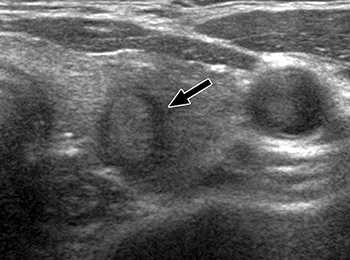

Существует 4 типа сосудистого рисунка щитовидной железы при УЗ-допплерографии:

- Отсутствие или слабая выраженность сигналов,

- Кровоток по периферии образования,

- Смешанный кровоток – по периферии и в центре узла,

- Только в центре узла.

К третьей группе заболеваний необходимо применять весь спектр имеющихся ультразвуковых методов исследования. Это исследование в обычной серой шкале, позволяющее оценить размеры узла, четкость его контуров, характер структуры, взаимоотношение с капсулой железы и окружающими тканями, провести динамическое наблюдение за выявленными изменениями. Нечеткость, неровность контуров узла, деформация капсулы железы, наличие кальцинатов в структуре узла – являются онконастораживающими признаками. Так же применение цветовой допплерографии позволяет оценить характер кровоснабжения узлов.